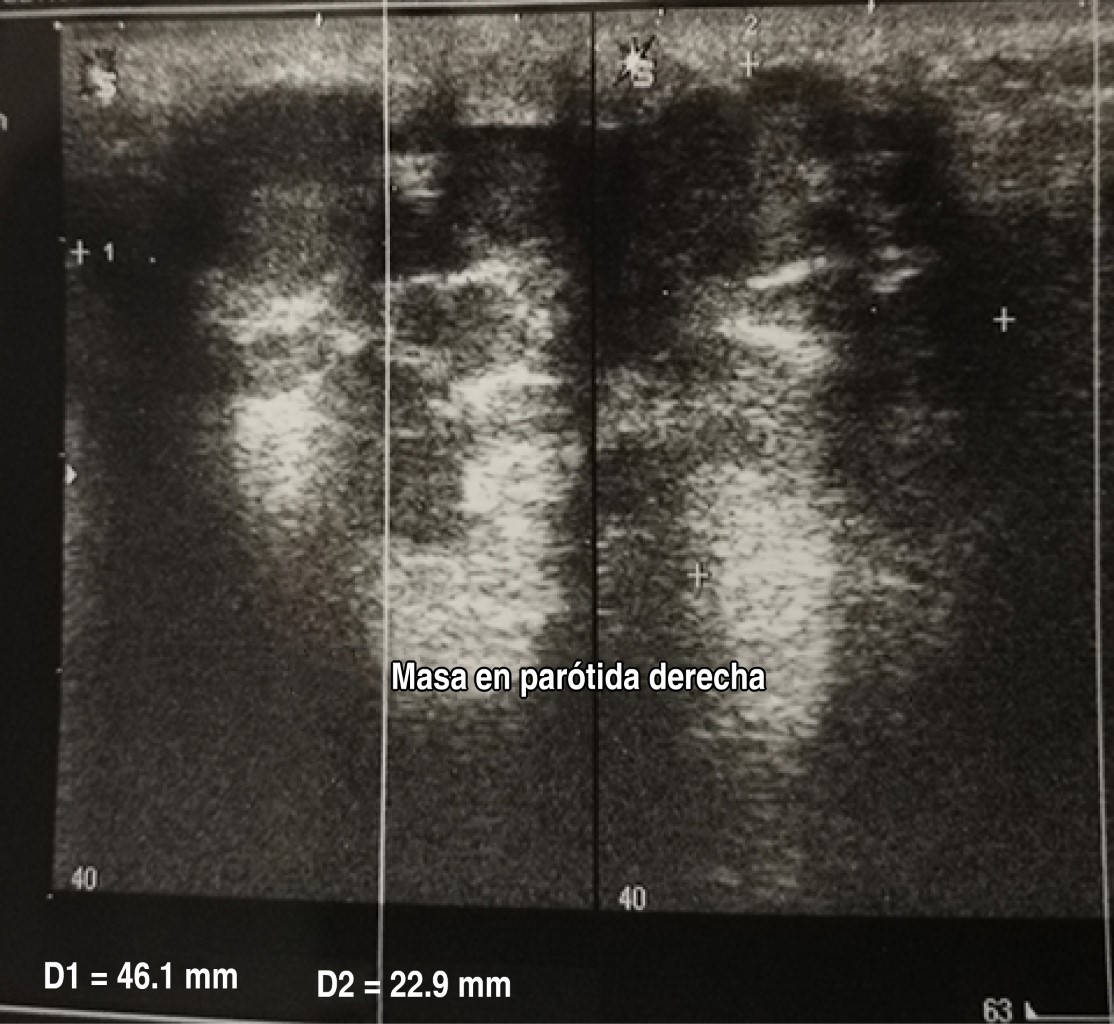

Figure 1

Figure 2

Figure 3

Figure 4

Figure 5

Figure 6

Figure 7

Figure 8

Figure 9

Figure 10

Figure 11

Figure 12